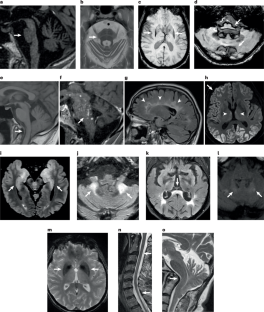

Carré, G. et al. Brain MRI of multiple system atrophy of cerebellar type: a prospective study with implications for diagnosis criteria. J. Neurol. 267, 1269–1277 (2020).

The authors thank Thibault Willaume from the Radiology Department of Strasbourg University Hospital for providing the imaging scan shown in Fig. 3o. J.H. declares that he is supported by a public grant overseen by the Agence Nationale de la Recherche (French Research Agency) as part of the Investissements d’Avenir programme (ANR-18-RHUS-0012) and by the European Reference Network Rare Immunodeficiency, Autoinflammatory and Autoimmune diseases network (RITA).

The authors contributed to all aspects of the article. Specifically, T.W. and M.A. jointly conceptualized the manuscript, which was coordinated by M.A. T.W. wrote the Abstract, the Introduction, the sections ‘Molecular causes of SLOCA’ and ‘Hidden genetic causes of idiopathic SLOCA’ (with C.D. and P.G.) and the Conclusion. T.W. prepared Figs. 1–4, Table 1 (with C.T.), Table 3, and Supplementary Fig. 1 (with T.K.). J.F. wrote the section ‘Biomarkers of disease trajectory’. J.H. wrote the section ‘Autoimmune and inflammatory causes’ and prepared Table 2. W.G.M. wrote the section ‘Multiple system atrophy’. C.T. wrote the section ‘Acquired causes of SLOCA’. T.K. wote the section ‘Towards disease-modifying treatments’. M.A. and E.R. synthesized all co-author drafts into the final version of the manuscript.